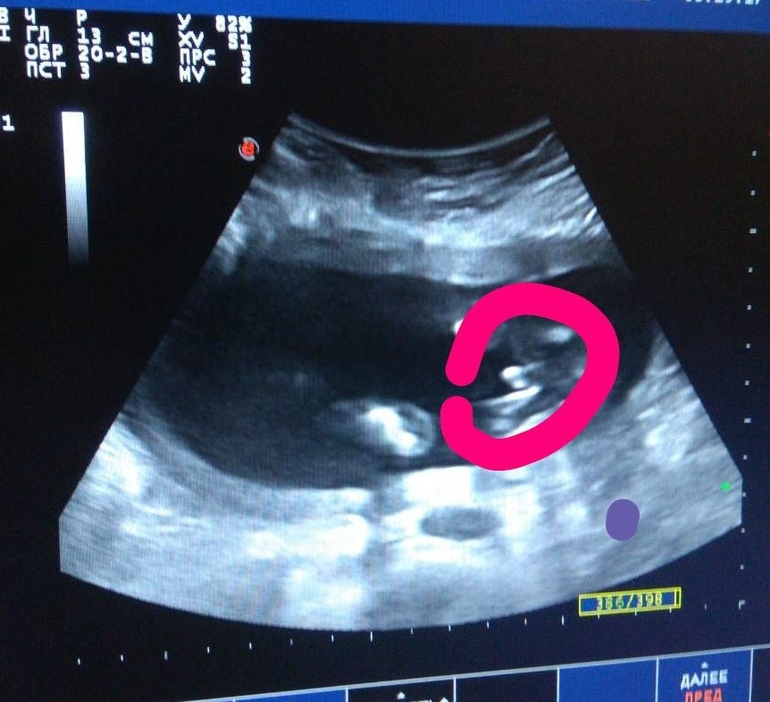

Второе плановое УЗИ и интрига раскрыта)))

Вот мы и прошли УЗИ и тройной тест, всё очень хорошо у нас, пока дождалась тройного теста чуть не свихнулась, ну а УЗИ это вообще чудо. Наш карапуз не стал прятаться и сразу же предъявил свой паспорт😆 На что наш папа прослезился - сын, гордость, второй продолжатель рода и фамилии.🤗 Развиваемся и растём по сроку, головкой вниз, плацента 0 зрелости, параметры плода все в норме. В общем всё хорошо. И мы безмерно счастливы, сегодня обрадуем сынульку, что у него будет братик, он так хотел именно братика👶

И фото с УЗИ, девочки, вы же видите, то что вижу

я и УЗИст?😁

да, видно богатство))